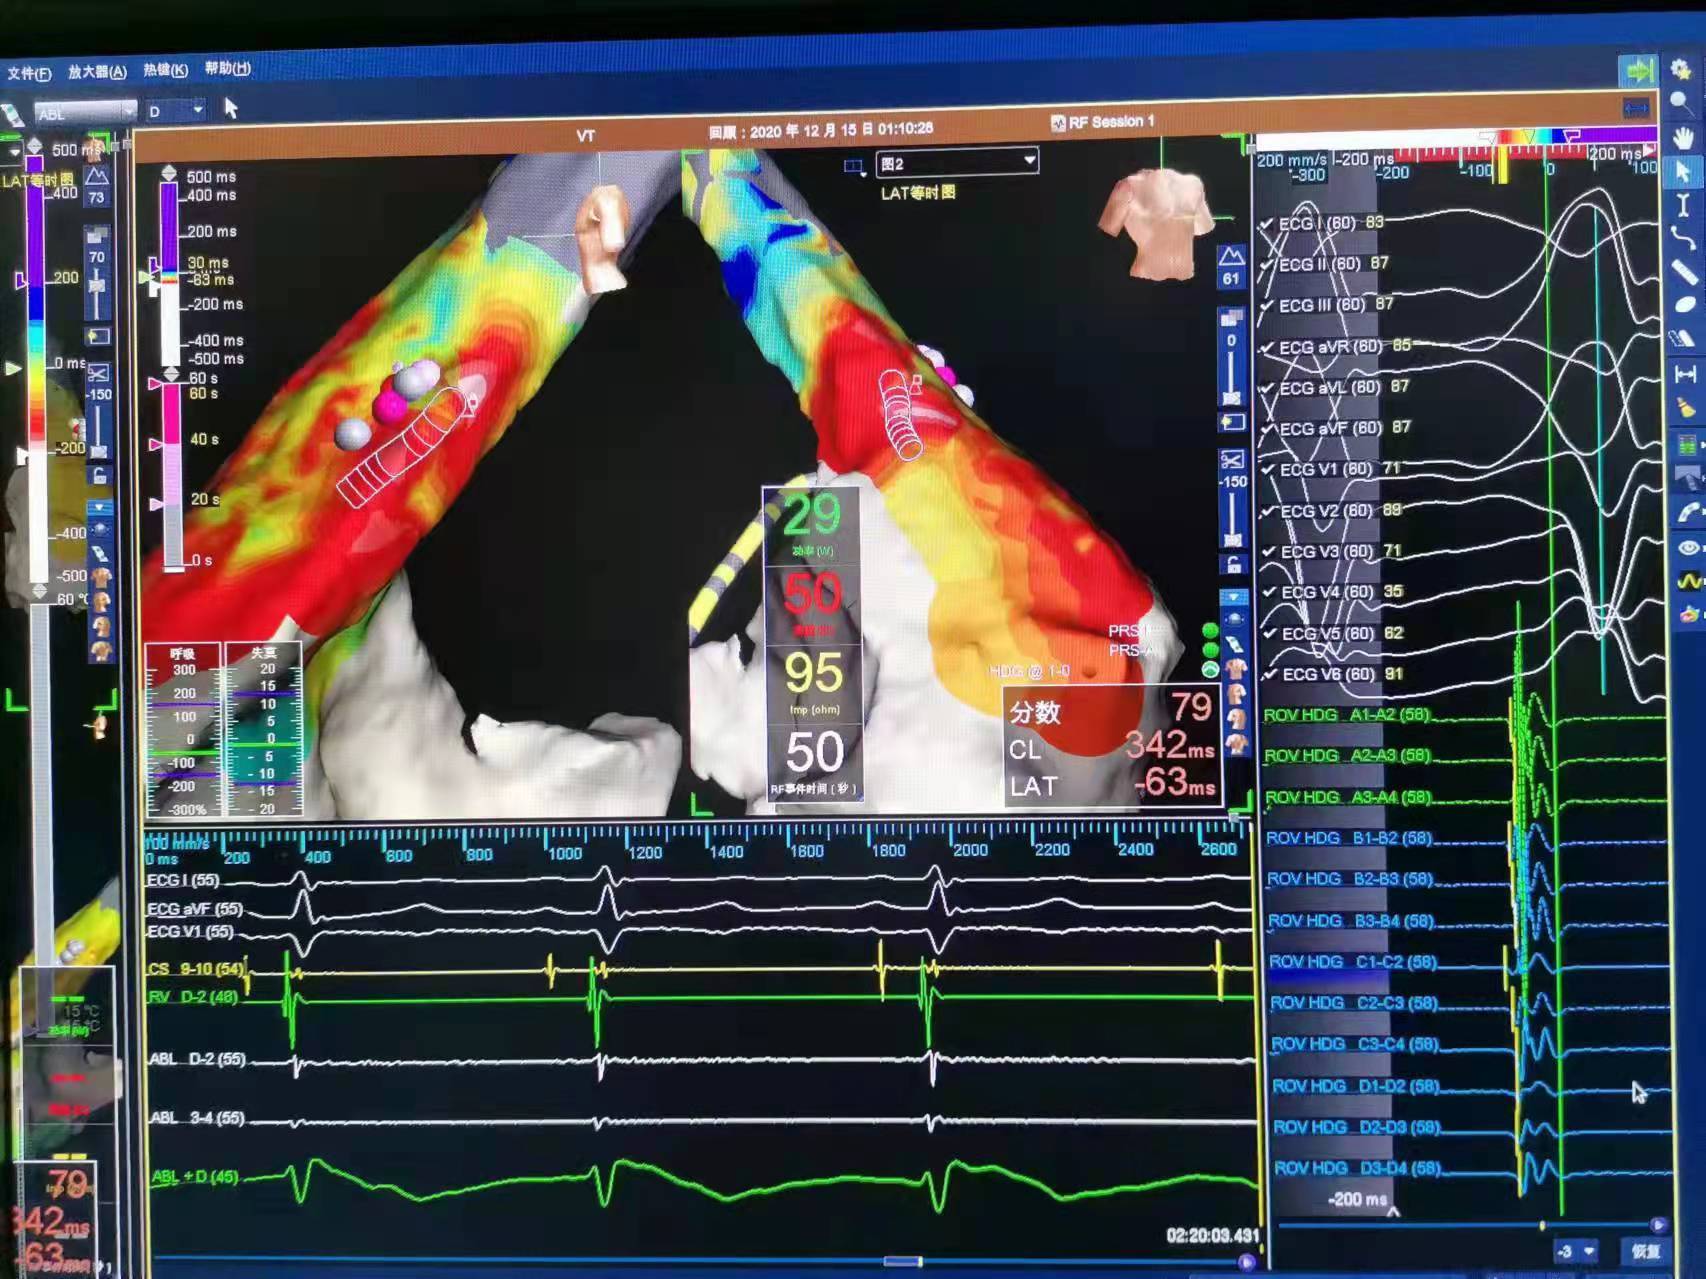

电生理标记三维图

经导管射频消融术是一种微创技术,它通过静脉血管途径将电极导管插入心脏,用电生理标测技术找到心脏内异常电传导通道或异位搏动点向患者病变部位释放射频电流,使局部组织产生凝固性坏死,达到阻断异常传导通道或消灭异位起搏点的目的,让患者心脏恢复正常跳动。该手术治疗方式具有治疗时间短、创伤小、恢复快、并发症小、效果好等优点,被广泛应用于临床。